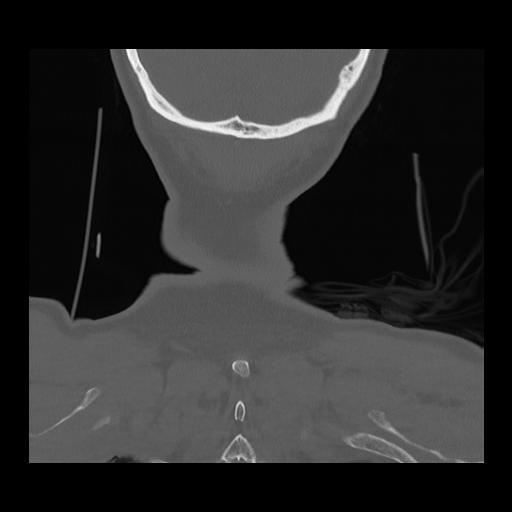

16 HUESO,,Coronal,2.000,HUESO,Coronal,